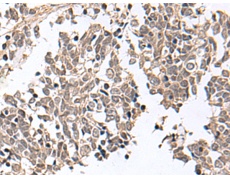

IHC positive control: |

Human cervical cancer and Human lung cancer |

IHC Recommend dilution: |

25-100 |